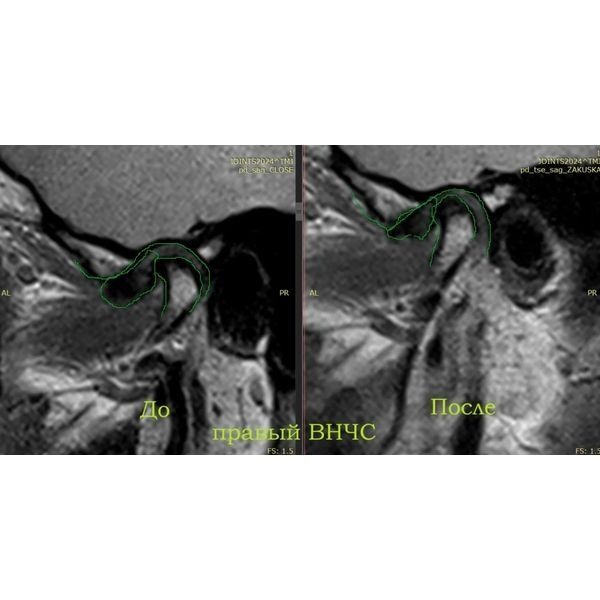

По результатам магнитно-резонансной томографии (МРТ) правого сустава:

- полное вентральное смещение суставного диска с редукцией — диск смещён вперёд, но при открытии рта суставная головка «запрыгивает» на диск;

- дистрофические изменения диска — диск начал терять эластичность и нормальную структуру;

- тенденция к перфорации промежуточной зоны диска — в средней части диска появляется риск возникновения сквозного отверстия;

- дорзальный тип установки головки мыщелкового отростка нижней челюсти — головка нижней челюсти стоит слишком далеко назад (дорзально) в суставной ямке (неправильное положение);

- остеоартроз ВНЧС 2-й степени по Kellgren — начальные дегенеративные изменения сустава.

При моделировании будущих зубов использовались данные аксиографии: угол суставного пути (наклон ската суставной ямки), переднюю направляющую (угол наклона центральных зубов), угол окклюзионной плоскости по сфере Монсона (высота боковых зубов). После провели примерку будущих конструкций в полости рта. Когда всё согласовали (женщина скорректировала эстетические параметры — размер и форму), конструкции зафиксировали на пару месяцев и сделали контрольное МРТ. Она показала расширение суставной щели и более корректное положение суставной головки слева.